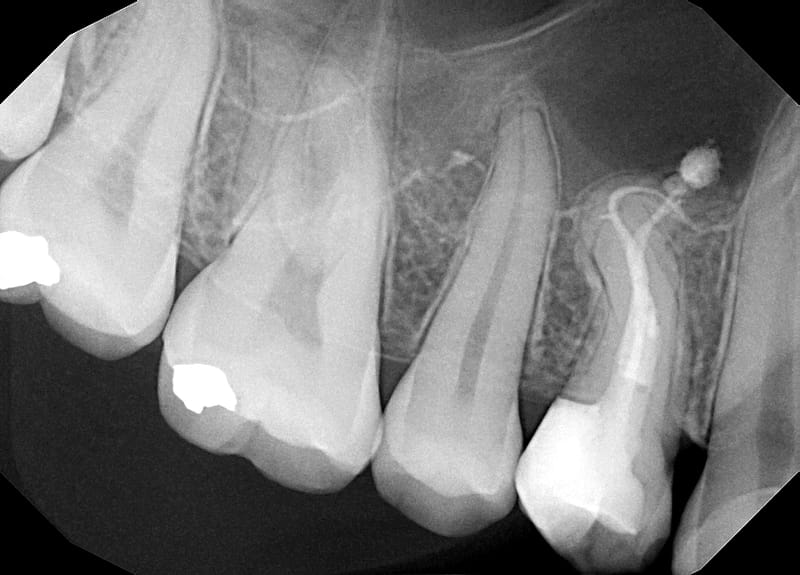

Leczenie pierwotne d.15